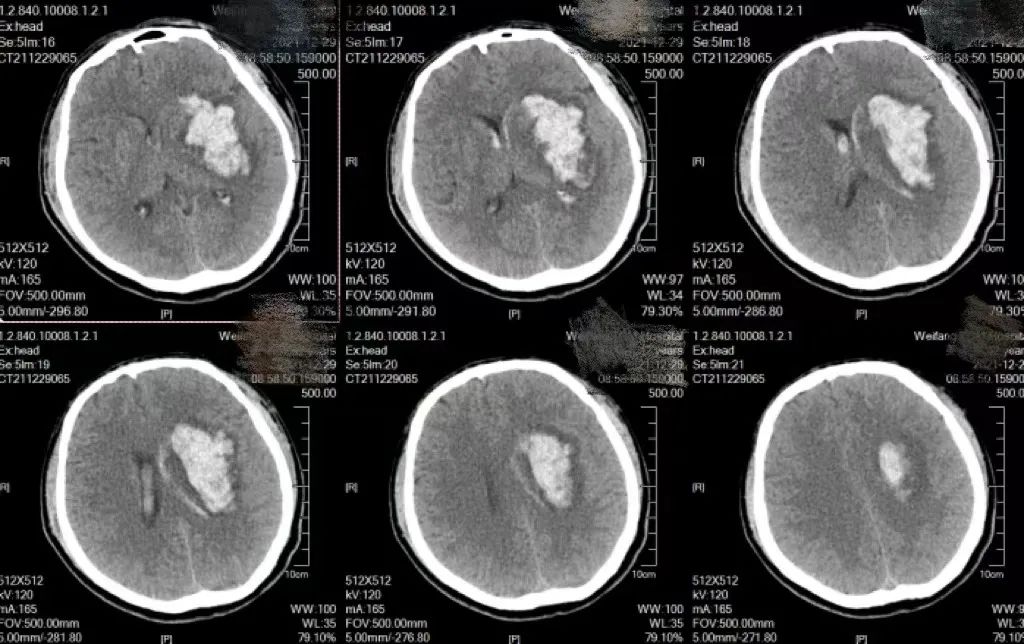

2021年12月,患者姜先生突发右侧肢体活动不利伴言语不能入院治疗。颅脑CT示左侧外囊出血,量较少,保守治疗。次日清晨患者出现肢体活动变差,昏迷,复查颅脑CT出血较前增加,大块血肿压迫脑组织,病情危重。

术后复查颅脑CT血肿清除满意,由于患者患有严重的肾衰,血钾报危急值,大大增加了患者的治疗难度,术后当天科室与血液透析室共同分析沟通病情,制定个体化透析方案,提供床旁血液净化。